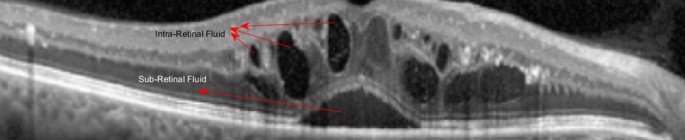

In this section, a new method is proposed for extracting the boundary pixels of cysts in the OCT images. At first, it should be noticed that a fluid-filled region in the retinal OCT image can be observed as a dark region formed between retinal layers or near the layer boundaries. The fluid-filled regions in the retina can be divided to Sub-Retinal Fluids (SRF) and Intra-Retinal Fluids (IRF). Both of them are presented in Fig. 2.

The basis for the boundary pixel determination phase is to find the vertical intensity changes during the image columns. Then, the points at which a significant vertical change is observed are determined. For each of these points, a rectangular patch is considered in the left and right sides. In the rectangular patch, we look for the points at which a significant diagonal change can be observed. If the patch includes a sufficient number of points with such a characteristic, the first point can be considered as a candidate for being a boundary pixel for cyst.